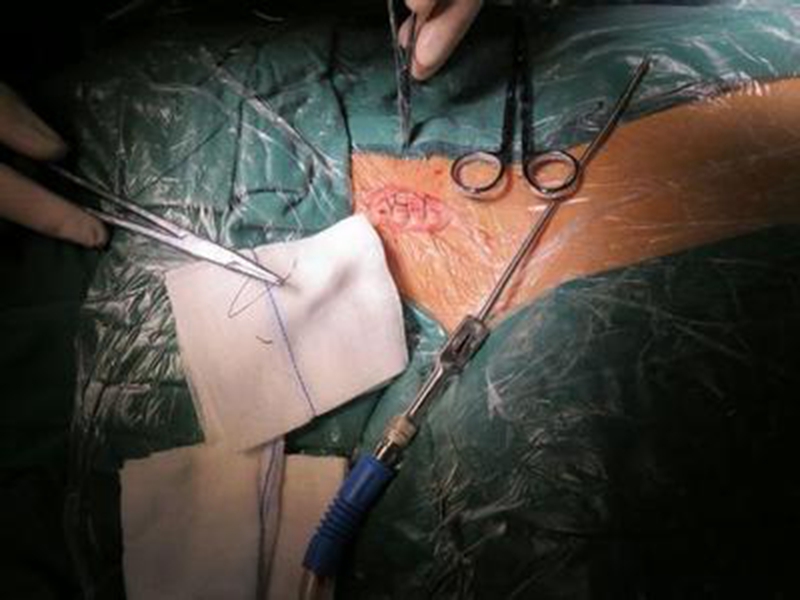

幼兒頸部手術煙霧病